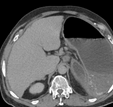

Contrast-enhanced CT of the abdomen, revealing air in intrahepatic biliary tree (pneumobilia) (red arrow)